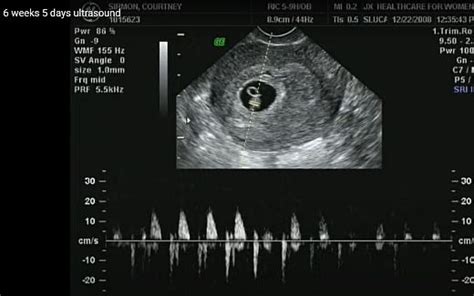

A megtermékenyüléstől számított negyedik hét vége felé már megdobban a baba szíve. A 10. héttől kezdve a magzat reagál az érintésre, ami annyit tesz, hogy elhúzódik arról a területről, ahonnan nyomogatást, kopogtatást érez.